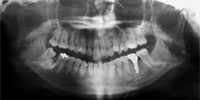

吉本歯科医院では、口内写真とパノラマレントゲンを撮影し、まずは顎の骨の状態まで詳しく確認しました。

虫歯の進行により歯の根っこに膿ができ、歯の周辺の骨まで溶け出している。.

・虫歯の進行により、歯の根っこに膿ができ、歯の周辺の骨までごっそり溶けてしまい歯がグラグラと揺れだした。

・親知らずを放置していたことにより、健全な歯を横に押し出し全体の咬み合わせのバランスを崩し、歯並びが悪く、不自然な力で噛み続けていたため歯が揺れだした。